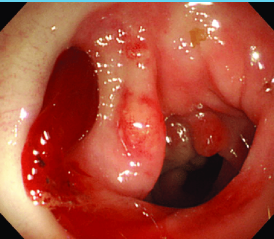

mucosa, biopsy, apple core

Colorectal Cancer: Diagnosis

-Colonoscopy (preferred)

Endoluminal mass arising from ______

Bleeding may be present

______ must be done to confirm diagnosis